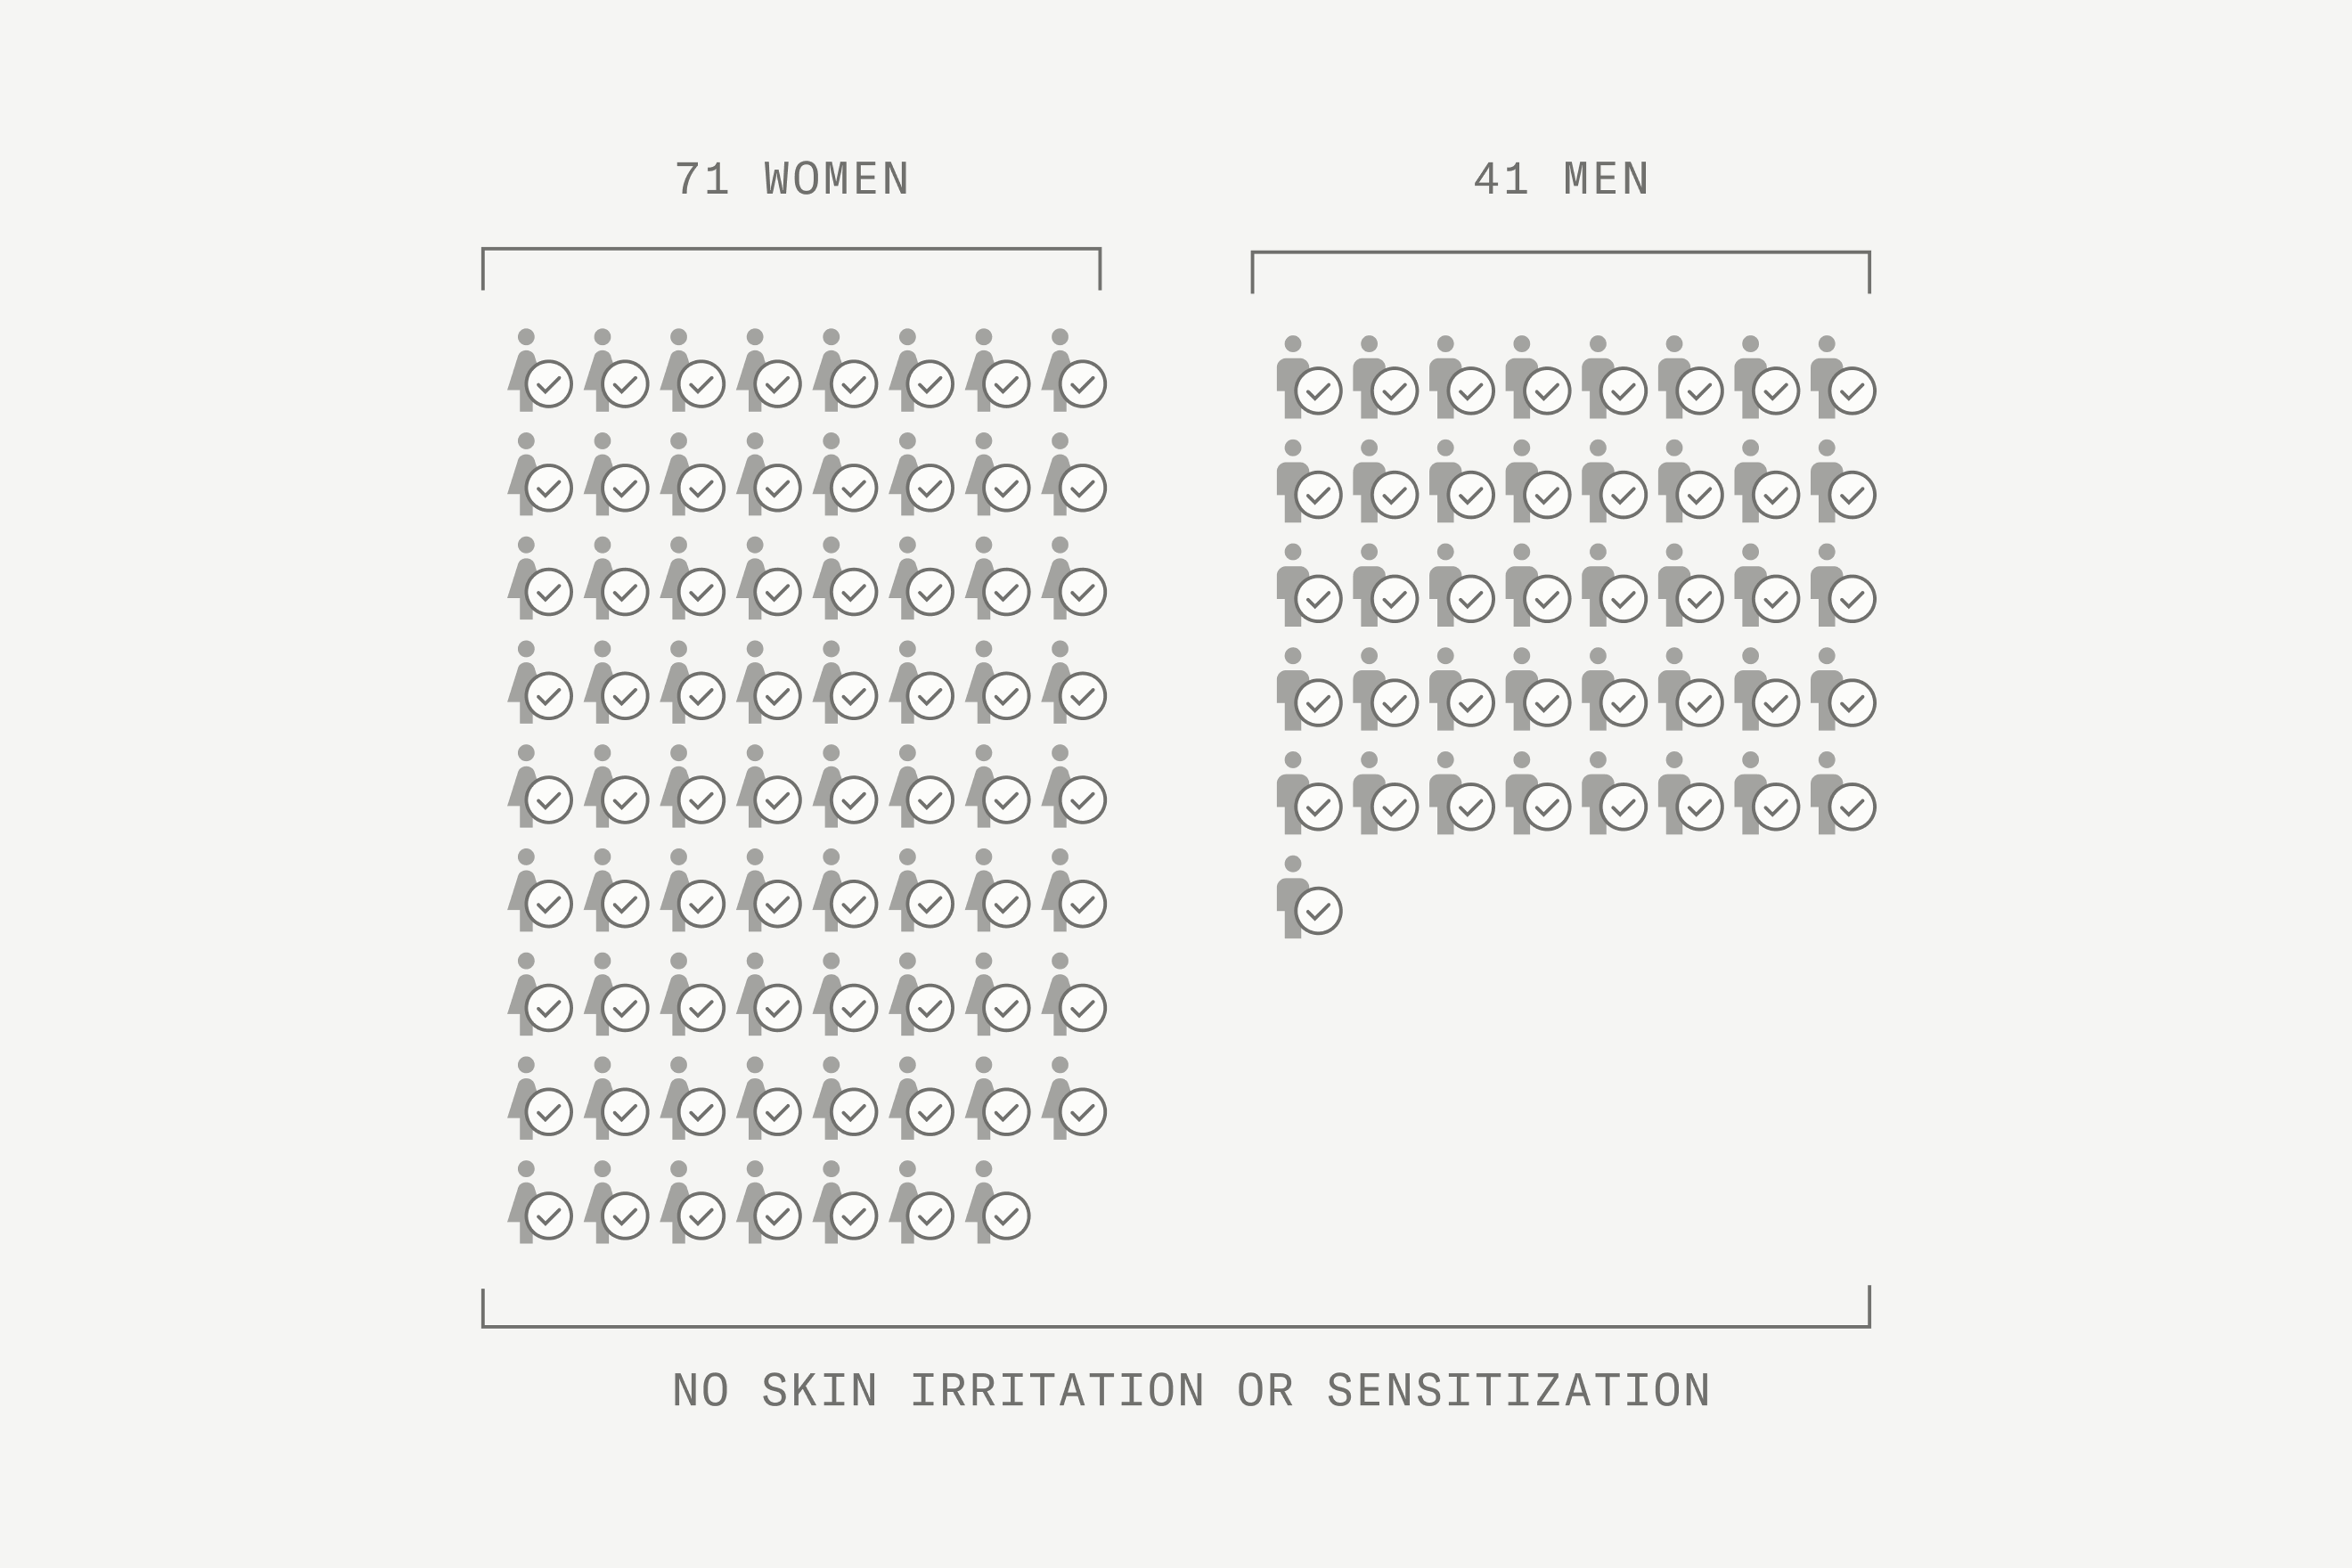

On top of all these benefits Mitopure is kind to skin - hypoallergenic and non-irritating

Mitopure® is gentle on the skin

The evidence for Mitopure® and its role in cellular vitality is impressive, but none of that matters if it irritates the skin. The good news is that the Swiss scientists who pioneered Mitopure® also tested it for safety – and across 112 subjects saw no irritation or sensitivity at all!

Mitopure® is dermatologist tested and approved as safe, kind to skin, and hypoallergenic. So, you can use products containing Mitopure® with confidence.

Internal Amazentis study 3: Dermatologically tested on 112 men and women. Safety and tolerability demonstrated using a human repeat insult patch test with Mitopure 1% in a base cream